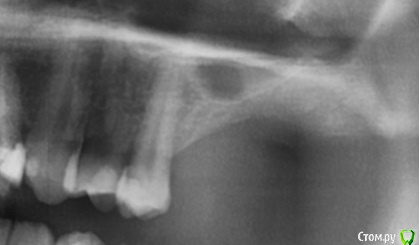

kamranchick Опубликовано 22 апреля, 2018 Поделиться Опубликовано 22 апреля, 2018 (изменено) Пациент после открытого синуса 2 месяца прошло, какие мысли коллеги? что делать, ничего не беспокоит, во рту все стабильно. Изменено 22 апреля, 2018 пользователем kamranchick Ссылка на комментарий